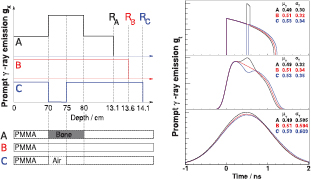

In clinical practice, range deviations are often caused by inhomogeneities along the proton track. Thus, a necessary next step towards the application of PGT under therapy conditions is the investigation of inhomogeneous targets. In the following we analyze prompt γ-ray emission spectra caused by three inhomogeneous target scenarios (figure 14(left)): A: PMMA target with a 10 mm bone structure at 70 mm depth. The material composition is adapted from the NIST database, namely BONE_CORTICAL (H (4.7%), C (14.4%), N (4.2%), O (44.6%), P (10.5%), Ca (21%), density ρ = 1.85 g cm−3). B: Full PMMA target. C: PMMA target (density ρ = 1.19 g cm−3) with a 5 mm air-filled cavity at 70 mm depth.

Figure 14. Left: prompt γ-ray emission profiles for three inhomogeneous targets. A: PMMA with a 10 mm bone insert at 70 mm depth. B: Homogeneous PMMA. C: PMMA with 5 mm air cavity at 70 mm depth. Corresponding gx profiles (simBox model) are given above. With respect to B, target A represents a beam undershoot by 5 mm, whereas C represents a beam overshoot by 5 mm. Prompt γ-ray production in the bone insert is assumed to be 1.6 times higher than in PMMA. Right: MC modeled prompt γ-ray time emission profiles gt, based on three different convolution kernels. Top: original gt profile, Middle: convolution with σΣ = 0.1 ns, Bottom: convolution with σΣ = 0.5 ns. Resulting gt mean values μγ and σγ are given in the graphs. The shift of μγ and σγ caused by a variation of the proton range is visible, values are discussed in the text.

Download figure:

Standard image High-resolution imageWe assume an initial proton energy of 150 MeV. Furthermore, the target thickness is assumed to exceed the proton range.

Taking B as reference, the proton range R is decreased by about 5 mm for A (beam undershoot), whereas R is increased by about 5 mm for C (beam overshoot). Figure 14(left) depicts the denoted targets and the assumed prompt γ-ray emission profile gx, assuming the simBox model. gx is zero within the air cavity. The ratio between gx in the bone structure and gx in the PMMA is 1.6, i.e. we assume that protons in bone produce 1.6 times more prompt γ-rays than in PMMA. This is a rough estimation based on our Geant4 simulations and data published by Polf et al (2009a). Polf et al report the ratio of prompt γ-ray production of compact bone being about 1.75 times higher compared to water.

Figure 14 shows the resulting modeled prompt γ-ray emission profiles gt. Analogous to figure 4 we depict the convolution of the respective gt distributions with Gaussian kernels of σΣ = 0.1 ns and σΣ = 0.5 ns. The shift of the proton range is clearly reflected in a shift of the mean value Δμγ of about 40 ps cm−1, not affected by the convolution, i.e. not affected by the system time resolution σΣ. The increased proton range (from A to C) is also expressed in a broadening of the gt distributions. However, with increasing width of the convolution kernel the range-variation induced difference of the standard deviation Δσγ is significantly reduced. A reasonable system time resolution σΣ is therefore highly desirable to improve measurement precision.

Note that, at this point, we constrain the analysis of the inhomogeneous target to an evaluation of gt distributions and their respective convolutions. The inclusion of prompt γ-ray time-of-flight effects (given by a specific detector configuration), as it is discussed in section 3.3, is disregarded. The geometrical position of the detector defines a specific, however nonlinear deformation of the gt distribution dependent on  and d (see figure 5). gt distributions can be understood as PGT spectra of a detector situated at

and d (see figure 5). gt distributions can be understood as PGT spectra of a detector situated at  ° at a distance d ≫ R, where prompt γ-ray time-of-flight differences as well as detector solid angle effects along the proton track are negligible.

° at a distance d ≫ R, where prompt γ-ray time-of-flight differences as well as detector solid angle effects along the proton track are negligible.

Based on the presented modeled data, we conclude that the PGT method is applicable for inhomogeneous targets as well. A comprehensive analysis of inhomogeneous targets (variation of target materials, size and position of inhomogeneities, beam energy etc.) goes, however, beyond the scope of this paper.